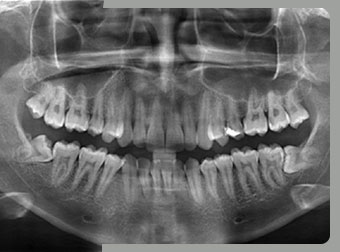

An orthopantomogram or an OPG, is a specialised or widescreen view of your lower face. It shows all your upper and lower teeth, as well as your jaws and jaw joints.

ADVANTAGES OF DIGITAL OPG

• Broad coverage of facial bones and teeth

• Low patient radiation dose.

• Convenience of examination for the patient. (Films need not be placed inside the mouth)

• Ability to be used in patients who cannot open the mouth or in patients whose mouth opening is restricted

• Patients ready understandability, making them a useful visual aid in patient education and case presentation

• Short time required for making the image.